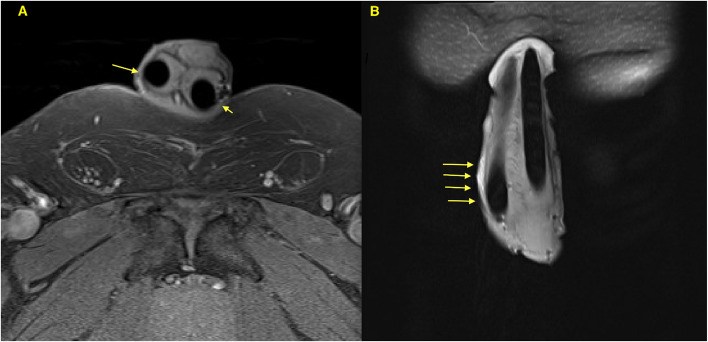

Background: The tunica albuginea is a key anatomical structure supporting penile implants. Several factors can lead to anatomical penile defects, contributing to penile prosthesis malfunction.The aim is to describe the consequences of malleable penile implant fractures, their contribution to tunica albuginea defects, and management outcomes.

Results: All patients underwent malleable device surgery were reviwed retrospectively in our center. We included three patients with malleable penile implant disruption. Two patients underwent concomitant plication corporoplasty (PC) with device replacemen and one patient with device replacement only that showed intact tunica albuginea. The mean age at revision was 71.3 years. All patients achieved device stability and reported successful vaginal penetartion after PC and device replacement, with a median follow-up of 28 months.

Conclusions: Malleable penile device fractures are extremely rare findings. They can cause tunica albuginea disruption and tears, compromising penile penetration and device stability. Device replacement combined with PC is an essential component of successful vaginal pentration.